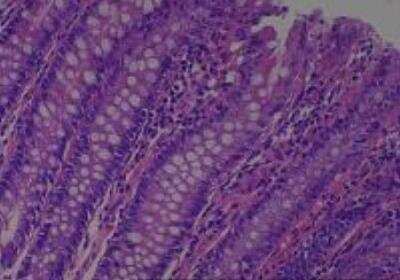

Hematoxylin & Eosin Stain: Human Common Tissue MicroArray (Normal Adjacent) [NBP2-30215] - 102. Stomach